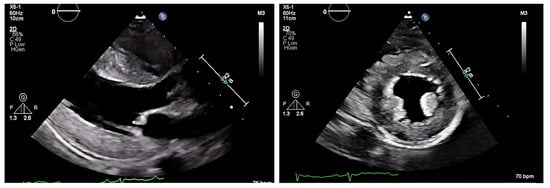

Next, we performed a 99Technetium pyrophosphate (99mTc-PYP) planar scintigraphy (Figure 4). A quantitative analysis of the heart retention pattern showed a heart-to-contralateral lung (H/Cl) ratio of 1.66 (Figure 5), strongly suggestive of amyloid deposition. To differentiate the type of cardiac amyloidosis, genetic testing was obtained and revealed a heterozygous pathogenic mutation in the TTR gene, diagnostic for TTR amyloidosis.

Radionuclide bone scintigraphy uses a bone-avid, phosphate-based isotope (99mTc-PYP) as a noninvasive way to diagnose ATTR. Phosphate-calcium binding seems to play an important role in the myocardial uptake of tracers, though the exact mechanism is unknown. Increased tracer accumulation in ATTR may suggest it has a higher calcium level than AL, and/or the duration of amyloid deposition increases uptake as ATTR has a more indolent course. Scoring cardiac uptake of the tracer is done via a semi-quantitative method using the Perugini grading scale (graded from 0–3). It visually compares tracer uptake in the myocardium and ribs of the planar image. 99mTc-PYP with abnormal uptake (grade 2 or 3) in the absence of a monoclonal gammopathy has a specificity and positive predictive value of 100% for diagnosing ATTR-CA. However, genotyping is still required to differentiate hATTR and wtATTR. If hATTR is present, first-degree relatives should be tested for the identified variant [25]. A heart-to-contralateral lung ratio > 1.5 has a 97% sensitivity and 100% specificity in differentiating ATTR from AL [28]. In patients with a monoclonal gammopathy, scintigraphy alone cannot be used to diagnose ATTR, and an endomyocardial biopsy (EMB) is required for diagnosis. Currently, imaging techniques allow for an accurate and noninvasive method to diagnose ATTR without the need for confirmatory myocardial biopsy. However, if you need to differentiate ATTR with concomitant MGUS from AL, an EMB is indicated. Lastly, a plasma cell dyscrasia with equivocal cardiac imaging findings is another indication for EMB [28].

Figure 4. SPECT in an ATTR cardiac amyloidosis patient. Evidence of uptake of 99mTc-PYP in the myocardium. (a) Quantitative SPECT/CT; (b) Semiquantitative analysis of 99mTc-PYP myocardial uptake.

Figure 5. Heart-to-contralateral ratio was calculated by drawing a region of interest over the heart, mirroring it to the contralateral chest, and calculating the ratio of heart ROI to contralateral chest ROI mean counts. The representative image demonstrates a H/CL ratio of 1.6. (H/CL, heart-to-contralateral; ROI, region of interest).